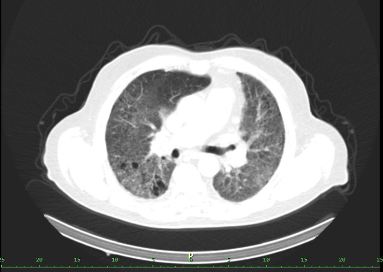

/ Obr. č. 8-10: ldCT plic v rámci vyšetření SPECT/CT. /

SPECT/CT potvrzuje tyto perfuzní defekty. Na ldCT je dále patrná Vámi popisovaná nespecifická intersticiální pneumonie, taktéž emfyzém, to však nevysvětluje diskrepanci mezi perfuzí a ventilací. Jde tedy o tzv. V/P mismatch.